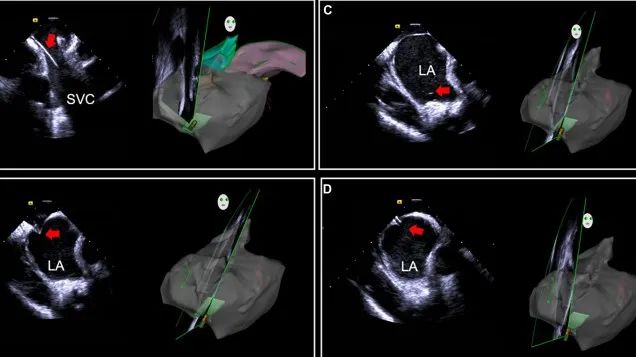

一種與心導(dǎo)管檢查相結(jié)合的超聲心動(dòng)圖診斷新興技術(shù),通過將超聲探頭置于心腔內(nèi)部,發(fā)射并接收超聲信號(hào),來精確獲取心臟解剖結(jié)構(gòu)、心臟血流動(dòng)力學(xué)等信息的實(shí)時(shí)成像。與其他影像技術(shù)相比,ICE技術(shù)具有操作簡單、無輻射、安全性高、手術(shù)效率高、實(shí)用等優(yōu)勢,ICE在很大程度上有望取代經(jīng)食道超聲心動(dòng)圖(TEE),成為電生理和結(jié)構(gòu)性心臟病領(lǐng)域的理想成像方式。

目前ICE技術(shù)已被應(yīng)用于左心耳封堵、房顫射頻消融、二尖瓣成形、房間隔缺損封堵等多種心臟介入手術(shù),應(yīng)用場景主要圍繞心臟電生理、結(jié)構(gòu)性心臟病等領(lǐng)域,目前以電生理應(yīng)用為主。數(shù)據(jù)顯示,我國結(jié)構(gòu)性心臟病介入器械市場規(guī)模已從2017年的4億元增長至2021年的20億元,年復(fù)合增長率達(dá)48.3%;預(yù)計(jì)到2025年,該市場規(guī)模將達(dá)到104億元,可以預(yù)見ICE市場規(guī)模也將同步高速增長,未來市場發(fā)展空間廣闊。

心腔內(nèi)超聲(ICE)技術(shù)壁壘極高,國內(nèi)主要廠商核心部件仍舊為進(jìn)口,集成了超聲和圖像處理最前端技術(shù),包括超聲探頭、線纜、軟件成像算法等,是當(dāng)前內(nèi)窺超聲方向最具挑戰(zhàn)的領(lǐng)域。ICE的應(yīng)用經(jīng)歷了2D平面成像、3D三維立體成像、以及4D的實(shí)時(shí)三維立體成像階段。